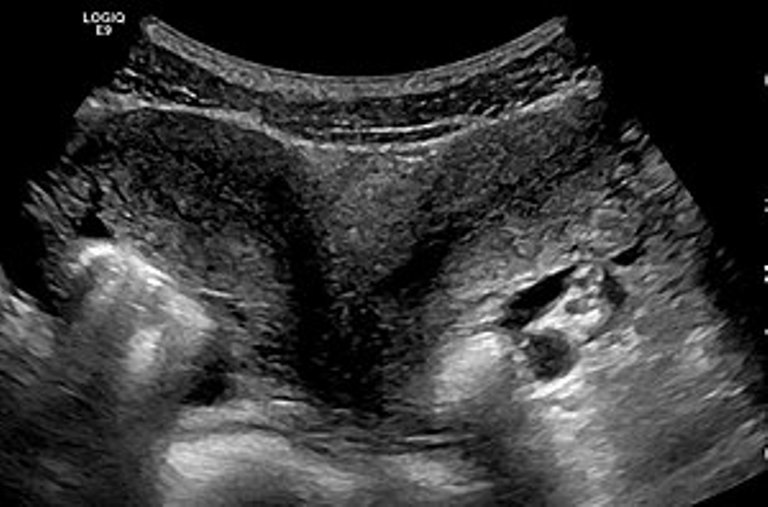

Doctors were shocked to discover she had another two babies. It was revealed that the mother had a double uterus – an incredibly rare condition a woman may have without realizing.

“The first baby was born from one womb. The two babies born here are from the other womb.”

Uterus didelphys, a condition that is present from birth, often causes no symptoms. Women who have a double uterus can successfully have children but it could increase the risks of premature birth or miscarriage.

While it affects one in 3,000 women, the odds of carrying a baby in each uterus at the same time are one in five million.